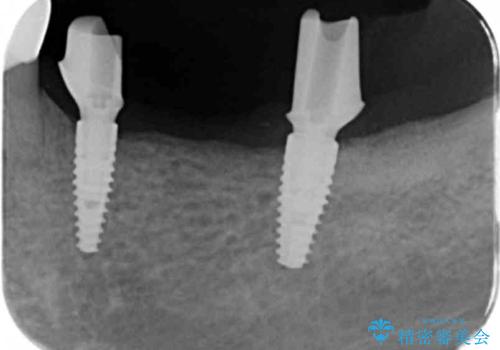

チタンカスタムアバットメントを用いた清掃性の高いインプラント治療

清掃のしやすさと審美性・強度に優れるチタン製カスタムアバットメントとジルコニアクラウンによる補綴治療を計画します。

- 113.3万円(インプラント×2・仮歯×3・チタンカスタムアバットメント×2・ジルコニアクラウン×3)費用は治療当時の料金となります

インプラント治療を行ったことでしっかりと噛めるようになり、また清掃性の高い環境を整備したことで長期的な予後も期待することができます。